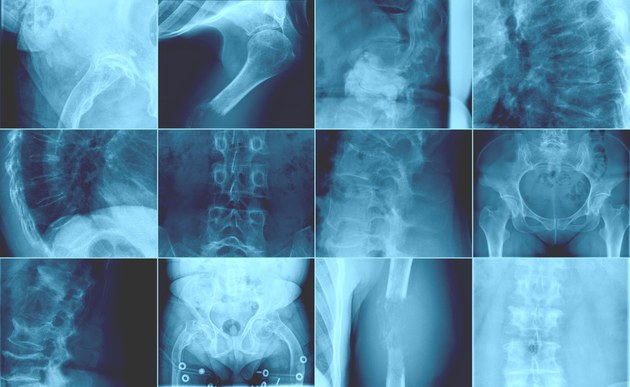

Knochenmetastasen sind häufige, teils schwere Komplikationen vieler Krebsarten im fortgeschrittenen Status. Metastasen bei Brust und Prostatakrebs, den häufigsten Krebsarten bei Frauen beziehungsweise Männern, siedeln sich vorrangig im Knochen an und können dort zu pathologischen Frakturen führen. Die Patienten leiden unter Schmerzen, ihre Beweglichkeit ist oftmals eingeschränkt und die Prognose eher schlecht. Neben Tumorzellen, die im Blutkreislauf zirkulieren, können auch disseminierte Tumorzellen im Knochenmark frühzeitig nachgewiesen werden. Viele Zelltypen, welche die Knochenmikroumgebung ausmachen, dazu zählen unter anderen knochenbildende und knochenabbauende Zellen, Zellen des Fettgewebes, der Gefäße oder des Immunsystems, stehen in engem Austausch mit diesen disseminierten Tumorzellen. Während manche dieser Zellen die Biologie des Tumors modulieren, werden andere durch die Tumorzellen selbst gestört oder gar verdrängt. Dadurch breiten sich Knochenmetastasen auf Kosten der blutbildenden Zellen oder der Immunzellen aus. Diese Wechselwirkungen werden in präklinischen und klinischen Studien untersucht. In einigen Therapieansätzen wird die Interaktion zwischen Tumorzellen und den knochenabbauenden Zellen gehemmt, wie bei Zoledronsäure oder Denosumab, was den Knochenverlust und zum Teil das Tumorwachstum hemmt. In anderen Therapieansätzen zerstört radioaktives Radium223, welches von den Knochenzellen ähnlich wie Kalzium behandelt wird, lokal Prostatakrebszellen im Knochen.